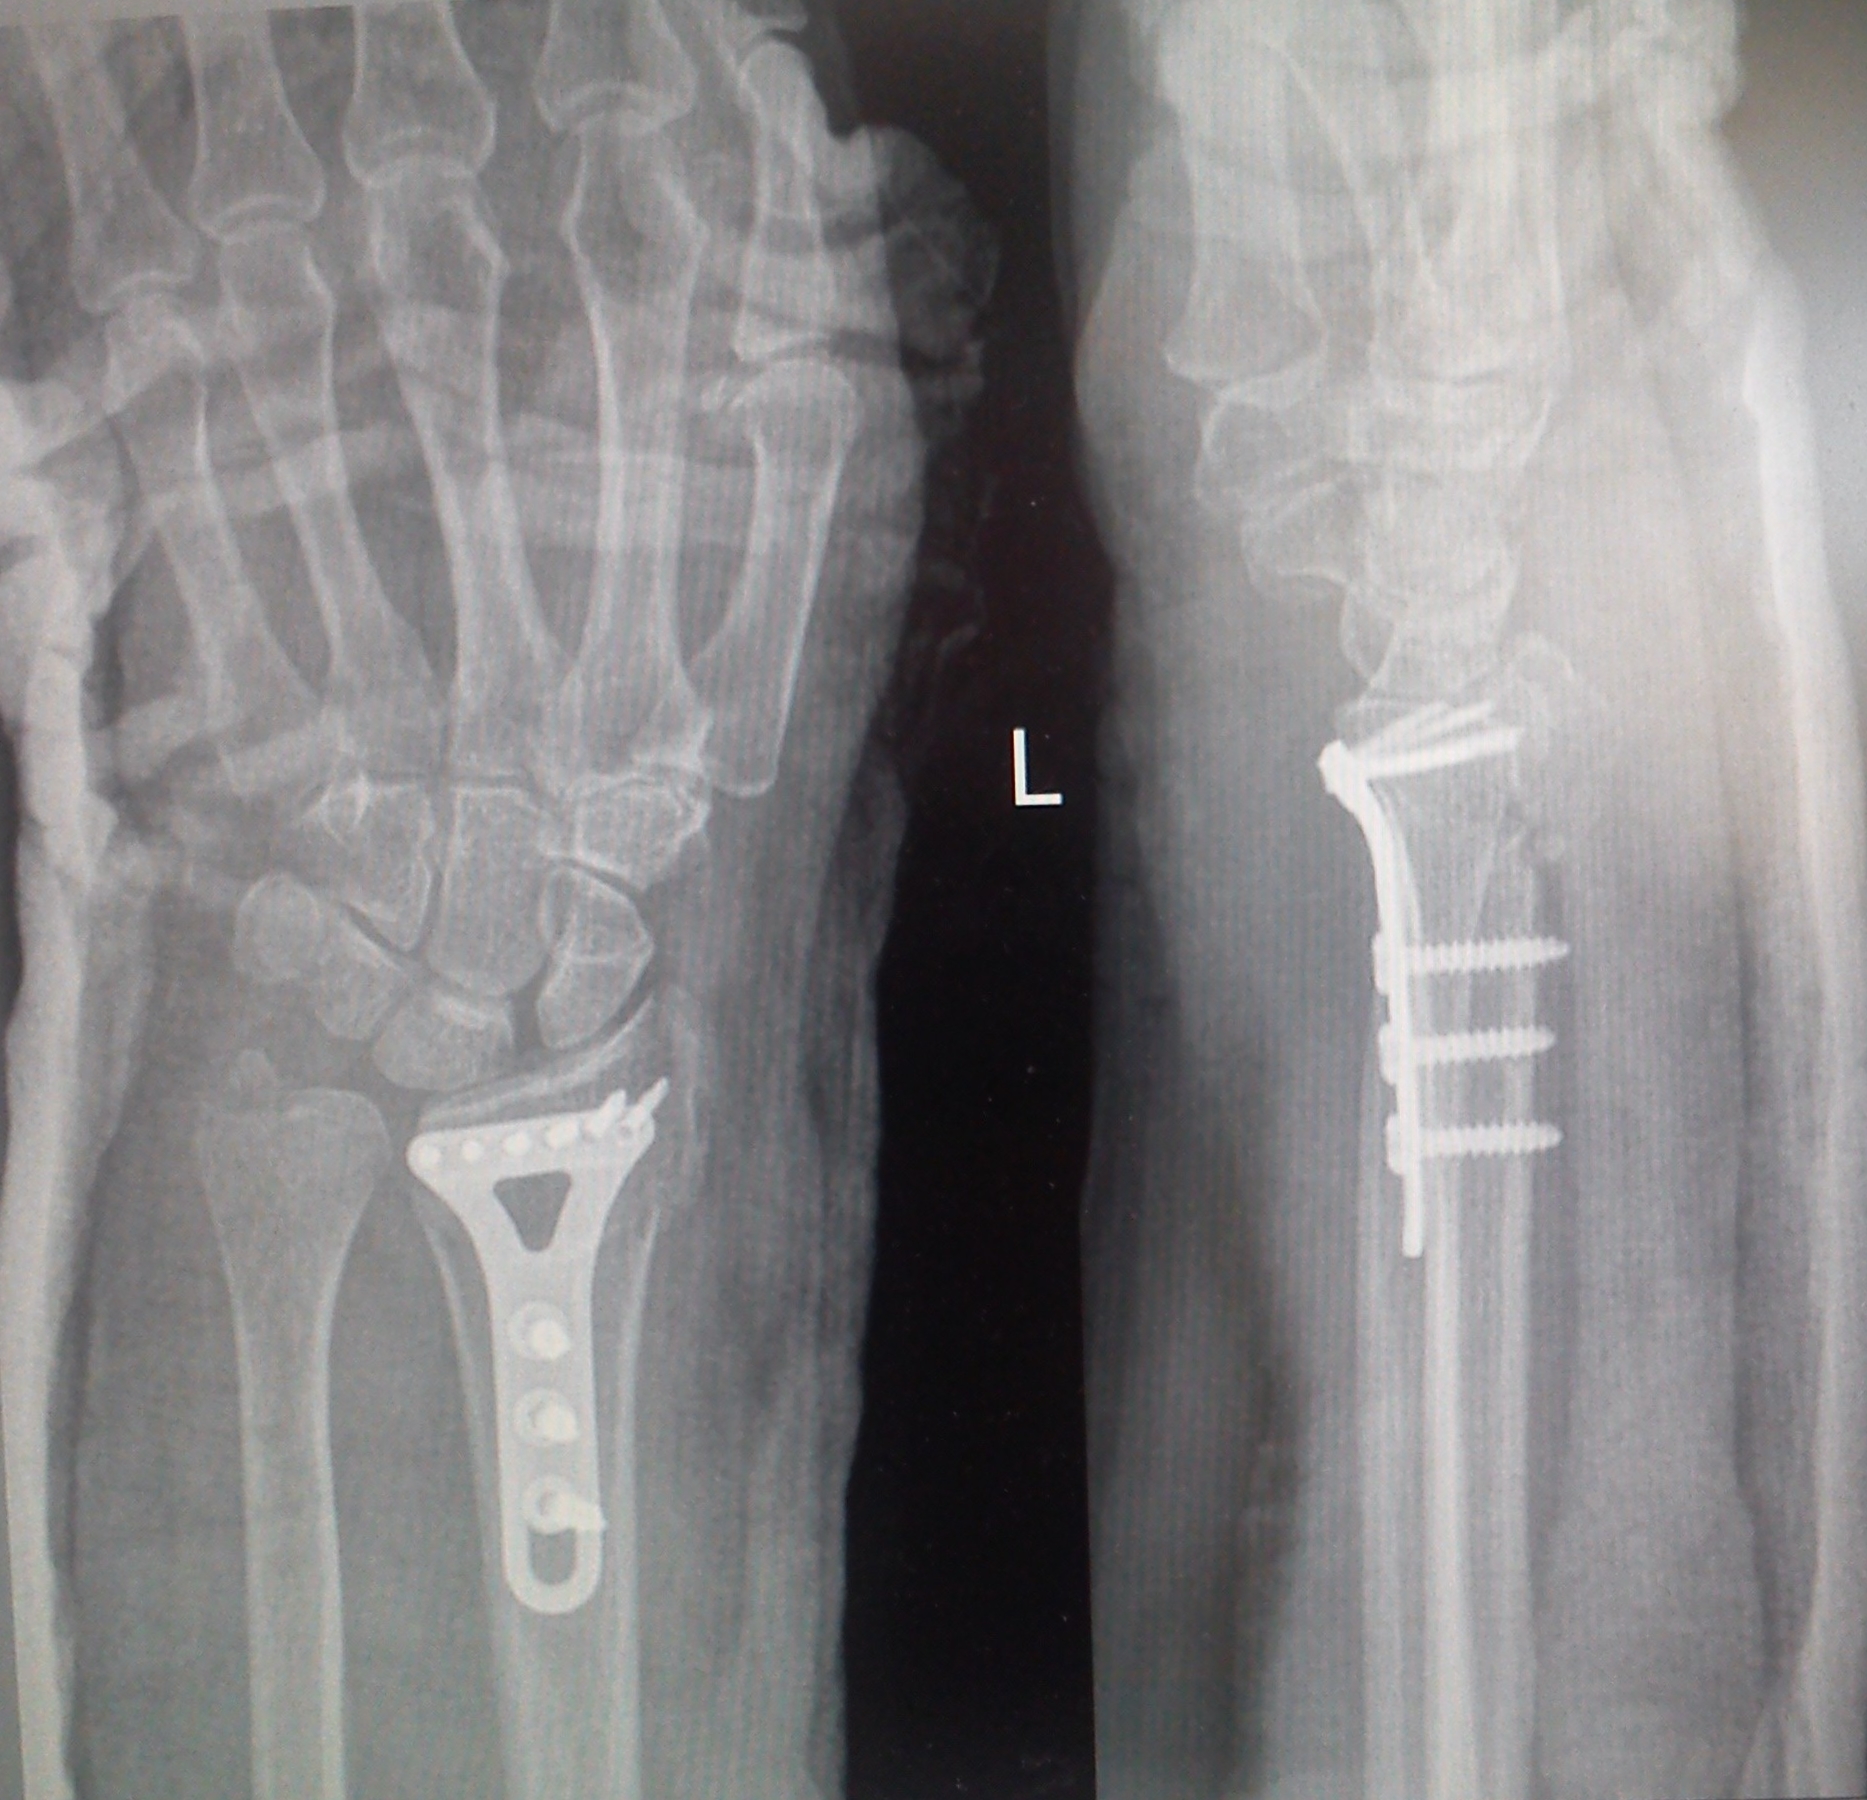

Изображения повреждения костей